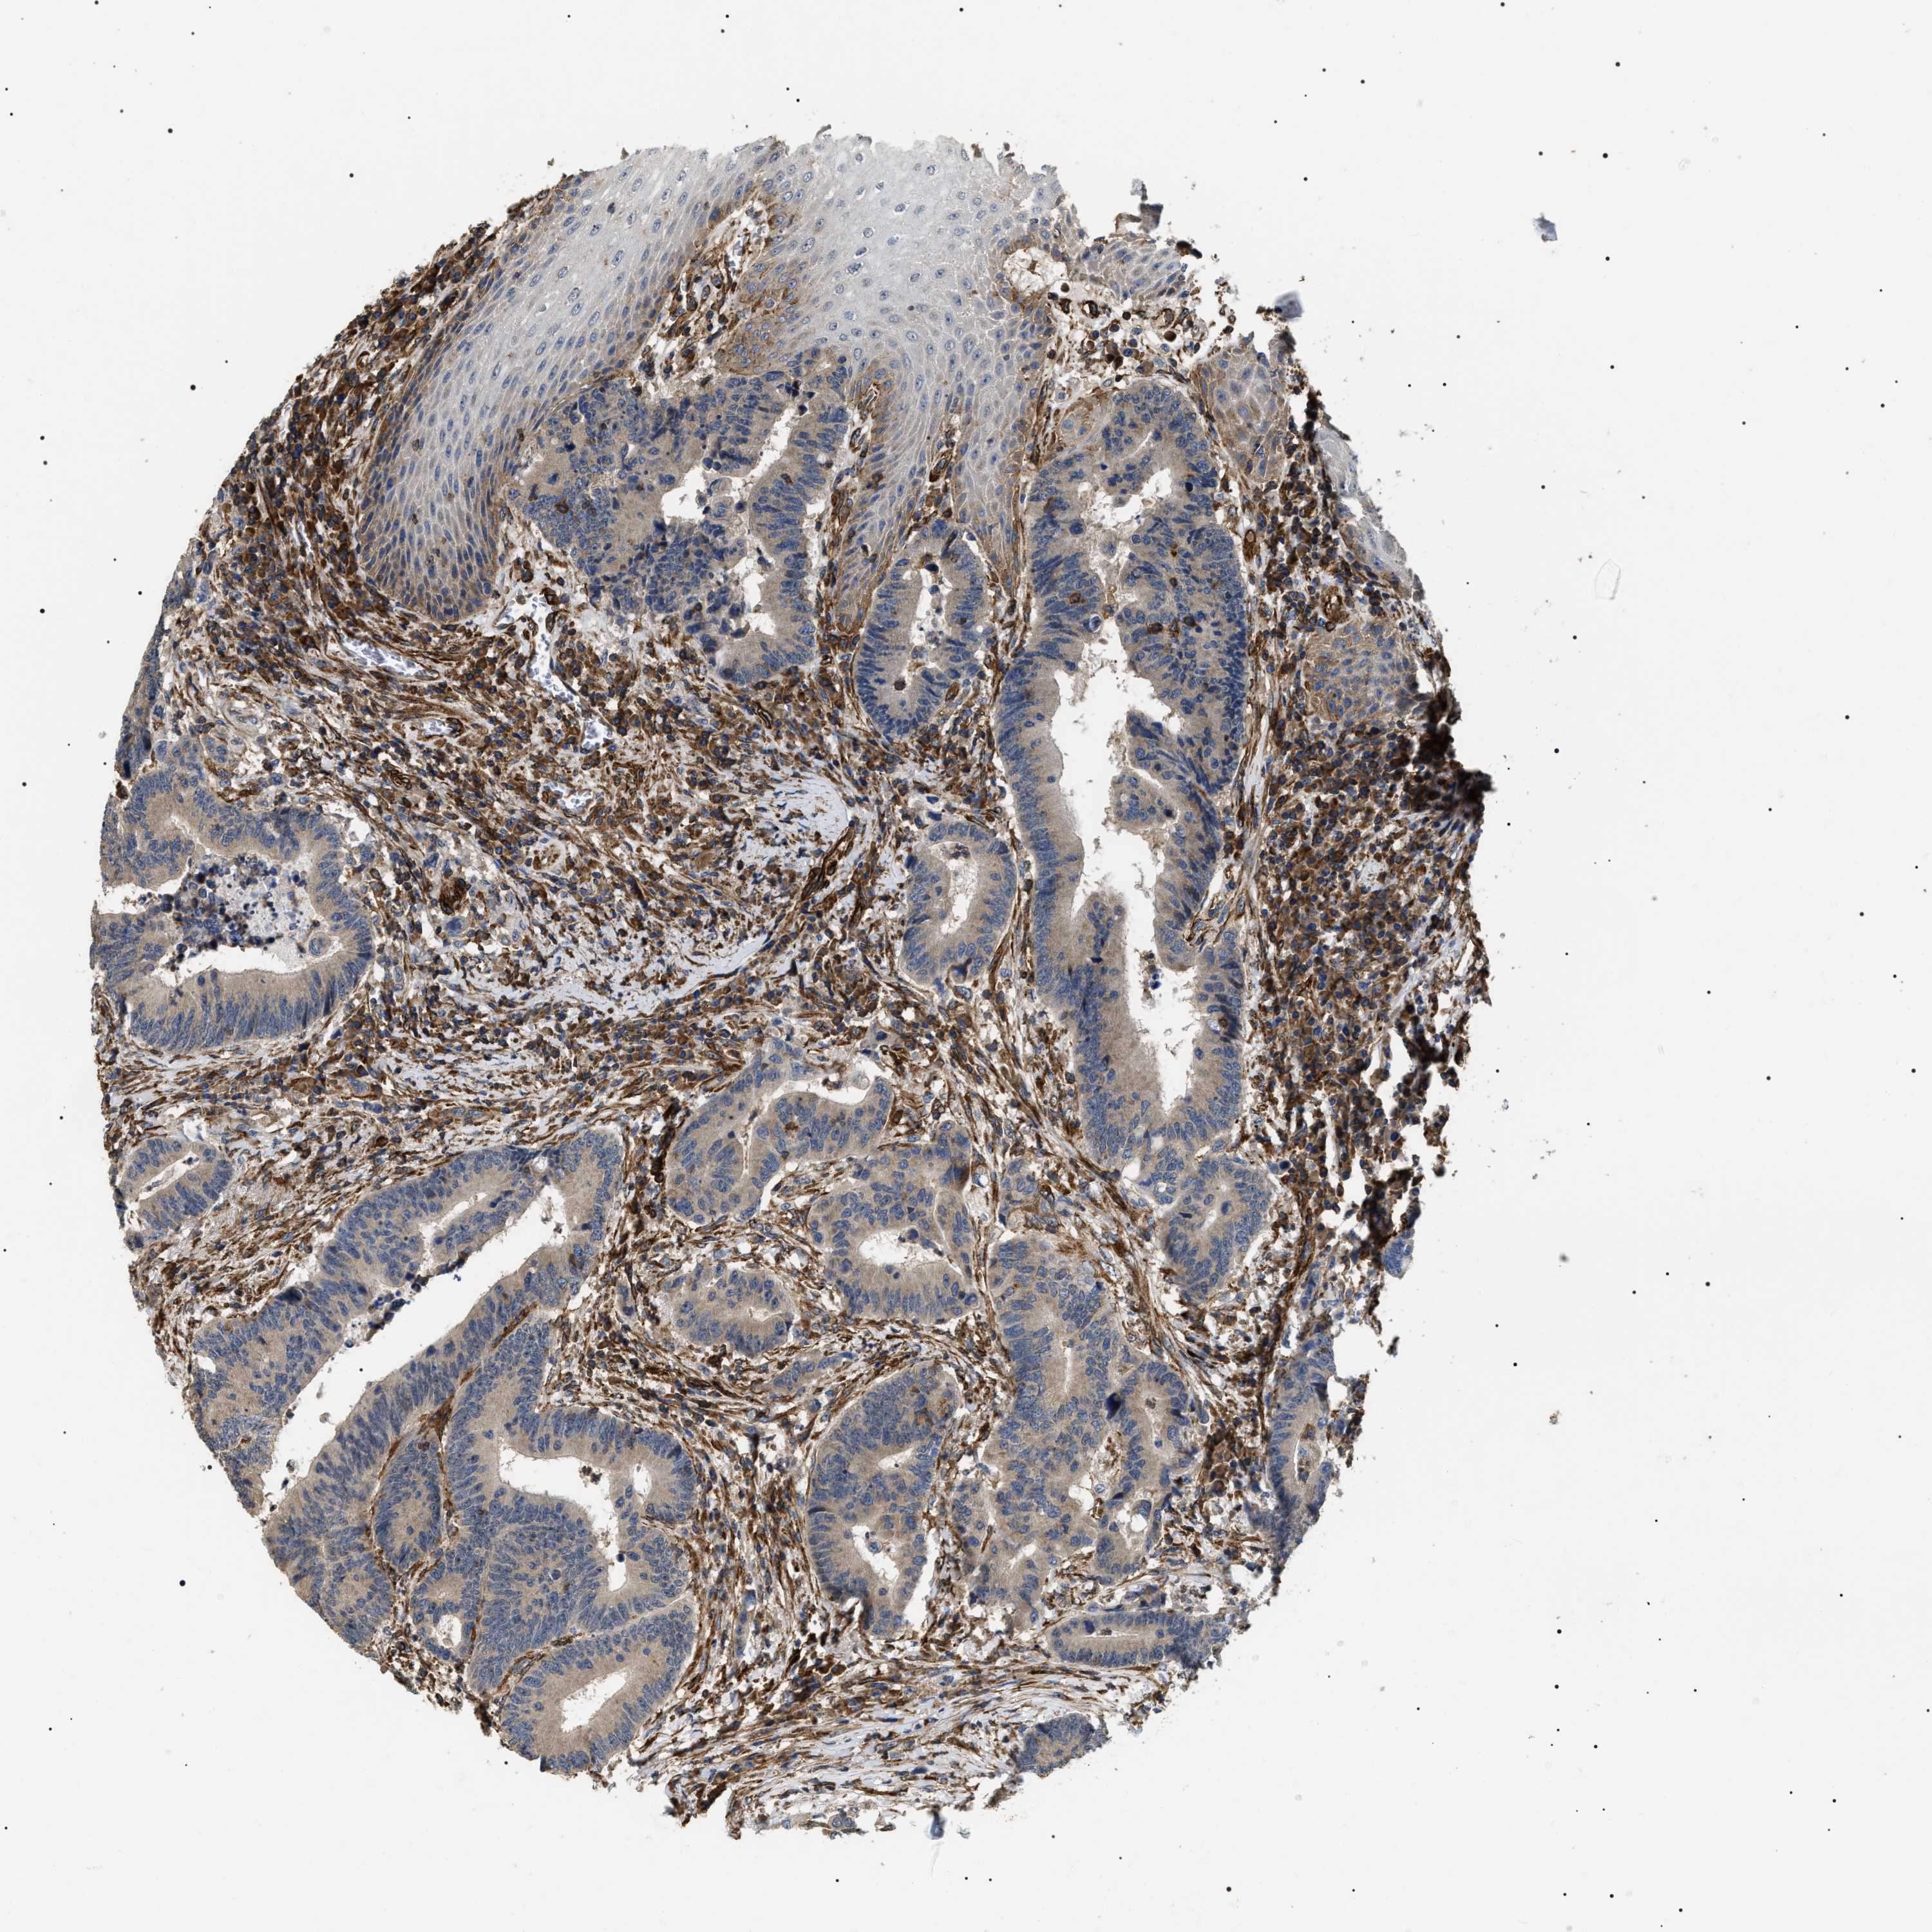

CANCER COLORECTAL CANCER Show tissue menu

Colorectal cancer

Human cancer

Colon adenocarcinoma